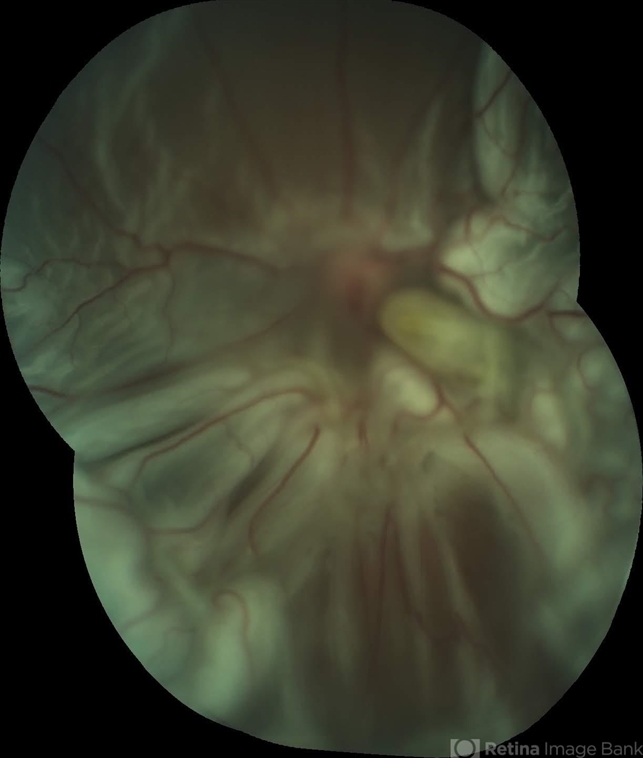

- proliferative vitreoretinopathy (PVR)

- Fundus photograph of a 34-year-old woman with a proliferative-vitreoretinopathy, observed 6 weeks after to be operated of vitrectomy + scleral buckle + SF6 20%. In the first visit presented rhegmatogenous retinal detachment and keratic precipitates.